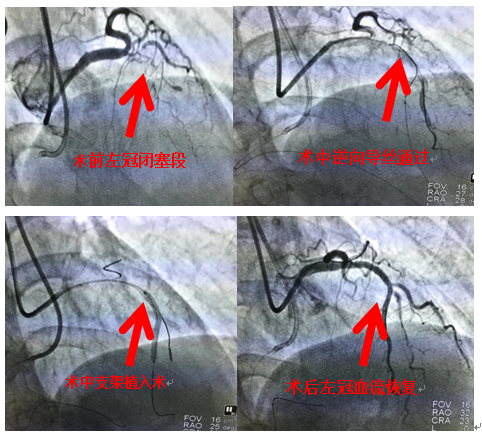

近日,南院老年心血管內(nèi)科對(duì)一位冠脈慢性閉塞病變(cto)患者成功實(shí)施cto病變逆向介入治療,術(shù)中綜合應(yīng)用了平行導(dǎo)絲、逆向?qū)Ыz、reverse-cart、rendevous等先進(jìn)技術(shù),最終成功完成雙側(cè)支架植入術(shù)。該技術(shù)在郴州地區(qū)乃至湖南地區(qū)處于領(lǐng)先地位,標(biāo)志南院老年心血管內(nèi)科介入技術(shù)取得了突破性進(jìn)展。

該患者為老年女性患者,因胸痛入住南院老年心血管內(nèi)科,冠狀動(dòng)脈造影確診左側(cè)冠狀動(dòng)脈(前降支)近端開(kāi)始就完全閉塞,右側(cè)冠狀動(dòng)脈形成側(cè)枝供應(yīng)左側(cè)前降支遠(yuǎn)端,但是自身遠(yuǎn)端也存在嚴(yán)重狹窄。老年心血管李維軍科主任立即組織老年心血管介入團(tuán)隊(duì)進(jìn)行討論后決定先行左側(cè)冠脈支架植入術(shù),嘗試正向cto技術(shù),如通過(guò)困難則行逆向cto技術(shù)。該患者最終使用逆向cto技術(shù)順利完成左側(cè)冠狀動(dòng)脈支架植入術(shù),并術(shù)后未出現(xiàn)并發(fā)癥。手術(shù)術(shù)者李維軍科主任,助手周玉慶主治醫(yī)師。